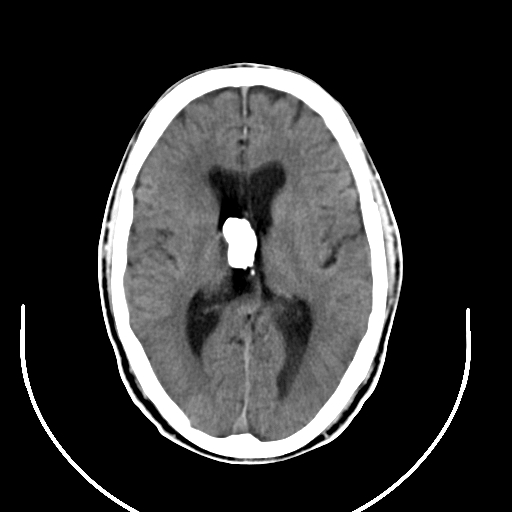

以下是引用拾荒者在2008-7-26 15:36:00的发言:[br]侧脑室内高密度钙化影,未见软组织结构,侧脑室未见增大,考虑良性钙化性改变(钙化型脑膜瘤可能)。

以下是引用宇宙ct在2008-7-26 13:43:00的发言:[br]支持:钙化性脑膜瘤。 不排除脉络膜瘤 [br] [br]